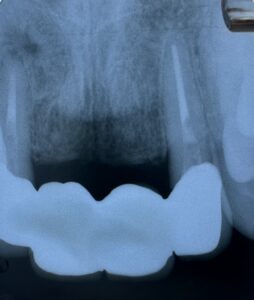

治療後 が 次の レントゲン写真。

若い 歯科医師が

この レントゲン写真を 観たら

根管充填剤 が 根管先端まで 入ってない じゃん❓️

お思いに なられる でしょうね。

でも

歯根膿疱

治って ますよ❗

レントゲン写真で 見える 歯根先端

生理学的根管先端 は

違い ます。